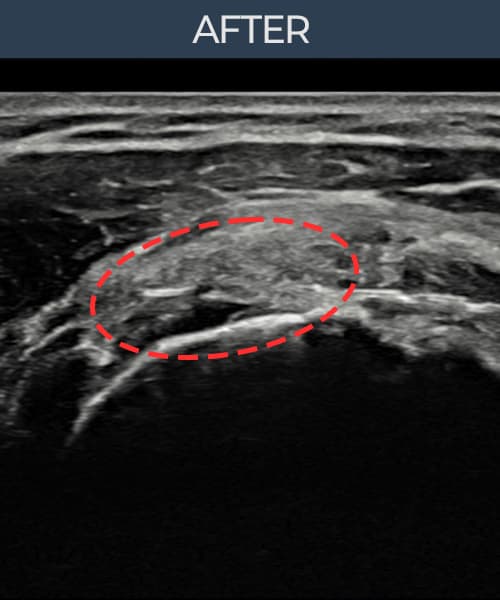

[経過期間: 23.07.31~23.09.27]

[縫縮術] 超音波検査にて左 棘上筋腱 부착부 광범위 部分断裂(13mm × 5mm (腱厚の約65%欠損))を確認。縫縮術施行後、腱の連続性が回復し、日常生活に復帰されました。